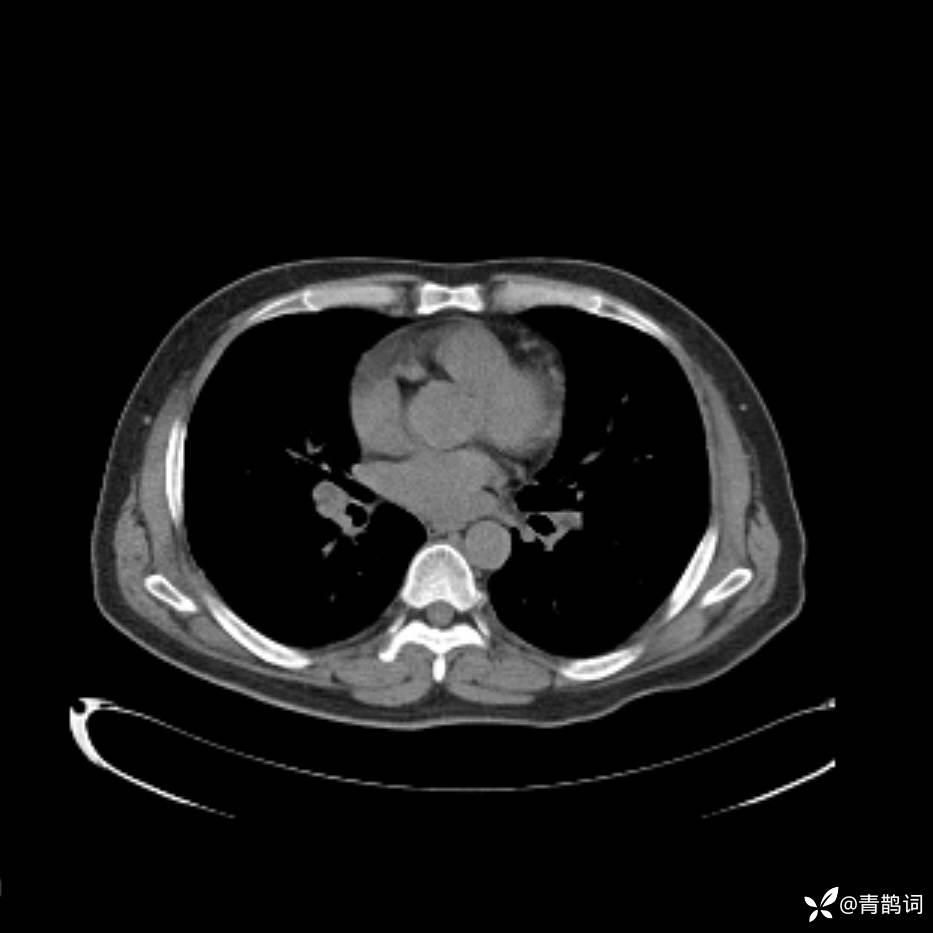

患者年龄:30岁。

患者性别:男。

简要病史:左颜面部肿胀2年,反复咳嗽咳痰,逐渐加重。

结合病史及影像学表现,期待评论区各位老师各抒己见~